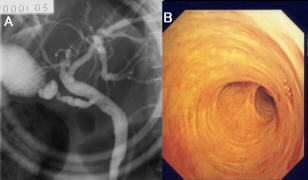

612 CARLO MONTI AND OTHERS December 1978 Fig. 2. Organic stenosis of the sphincter of Oddiin a 55-year-old man. This image shows marked dilatation of the common bile duct and"pencil ... View Document

Fig 1. (A) Magnetic resonance cholangiopancreatography revealed a biliary stricture at the porta hepatis and intrahepatic bile duct dilatation of the B5, B6, and B7 branches. ... Fetch Full Source